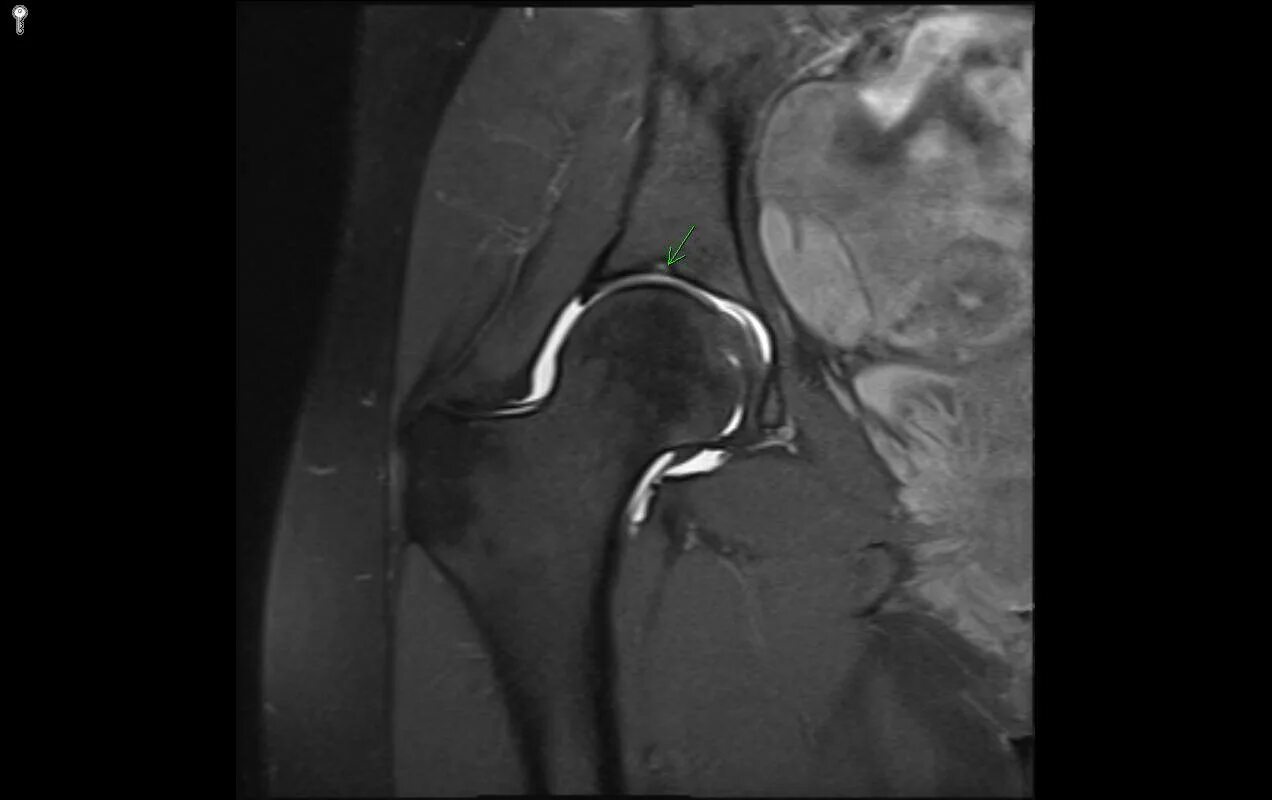

Мрт тазобедренного сустава в минске